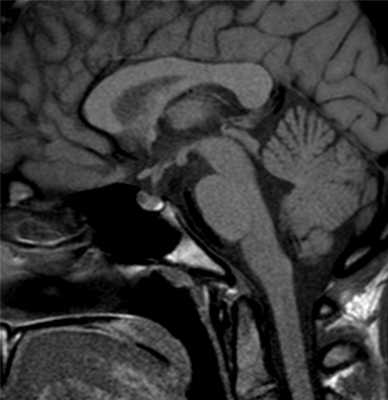

Киста кармана Ратке на МРТ

МРТ гипофиза при краниофарингиоме: сканы в разных проекциях

- киста кармана Ратке;

- краниофарингиома;

- арахноидальная киста.

МРТ гипофиза - киста кармана Ратке

Киста — это полое новообразование, заполненное жидкостью. Она носит доброкачественный характер и редко увеличивается в размерах. Самой распространенной формой кист гипофиза является киста кармана Ратке - образование, развивающееся между двумя долями гипофиза у основания головного мозга. Чаще всего киста кармана Ратке образуется во время эмбриологического развития из предшественника гипофиза. Диагностика данного кистозного образования возможна с помощью МРТ гипофиза. Признаками кисты Ратке на МРТ будет:

- на нативных изображениях между нейро- и аденогипофизом определяется зона измененного МР-сигнала с ровными четкими контурами, гипоинтенсивного МР-сигнала на Т1-ВИ, гиперинтенсивного на Т2-ВИ.